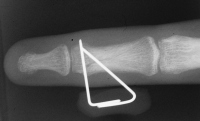

Case 3

Acute mallet fracture treated with percutaneous

pinning: proximal pin stabilizes the fracture

fragment, longitudinal pin maintains distal phalanx

position. |

| Thermoplastic bonding of the protruding ends: appearance at one month. |

| Late result. |